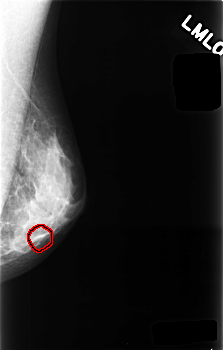

C_0477_1.LEFT_MLO

C_0477_1.LEFT_CC

LEFT_MLO LINES 4544 PIXELS_PER_LINE 2896 BITS_PER_PIXEL 12 RESOLUTION 50 OVERLAY

FILE: C_0477_1.LEFT_MLO.OVERLAY

TOTAL_ABNORMALITIES 1

ABNORMALITY 1

LESION_TYPE CALCIFICATION TYPE PUNCTATE DISTRIBUTION CLUSTERED

ASSESSMENT 4

SUBTLETY 3

PATHOLOGY BENIGN

TOTAL_OUTLINES 1

BOUNDARY